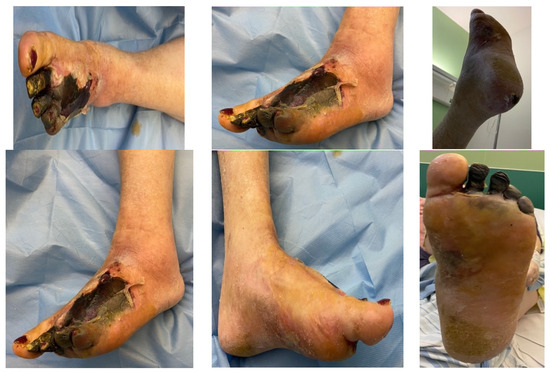

4.2. Case 2—Indirect Revascularization-Major Amputation